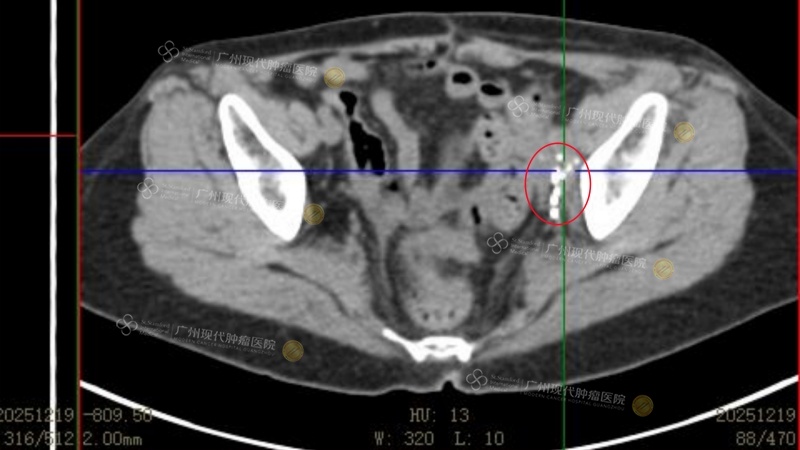

(Pelvis: Tumor reduced by 80% after two treatments) (The white highlights indicate the implanted particles)

(Re-examination on December 19, 2025, after four treatments, revealed that the tumor was essentially completely deactivated)

The results were swift and remarkable: After the first treatment session, the abdominal pain that had tormented her for so long disappeared. Following the second session, blood circulation in her leg was restored, and the swelling in her left leg significantly subsided. “This gave me tremendous confidence,” FOO AI KIM shared with excitement. “After the fourth session, a PET scan was done, and I could truly see the tumor had noticeably shrunk.” Over a period of three months, to date, FOO AI KIM’s pelvic lymph nodes have essentially been completely deactivated, the liver tumor has disappeared, and the overall efficacy assessment has reached PR (Partial Response).